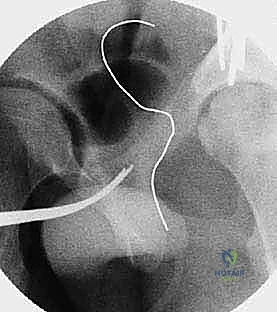

2. الأشعة السينية الرقمية (Digital X-rays): صور في وضعيات محددة (AP Pelvis, False Profile, Dunn view) لقياس زوايا التغطية (مثل زاوية CE وزاوية Tönnis).

4. الأشعة المقطعية ثلاثية الأبعاد (3D CT Scan): تُستخدم للتخطيط الجراحي الدقيق، حيث تتيح للدكتور هطيف بناء نموذج ثلاثي الأبعاد لحوض المريض وتحديد زوايا القطع قبل دخول غرفة العمليات.

القطع الأول: القطع الإسكي غير المكتمل (Incomplete Ischial Osteotomy)

باستخدام إزميل خاص ذو زاوية (Angled Osteotome)، يتم إجراء قطع في عظم الإسك أسفل الحُق مباشرة (في الأخدود تحت الحُقي). يتم هذا القطع بتوجيه الأشعة السينية (Fluoroscopy) لضمان عدم اختراق المفصل. يحرص الدكتور هطيف على إبعاد العصب الوركي والأوعية السدادية بأمان تام.